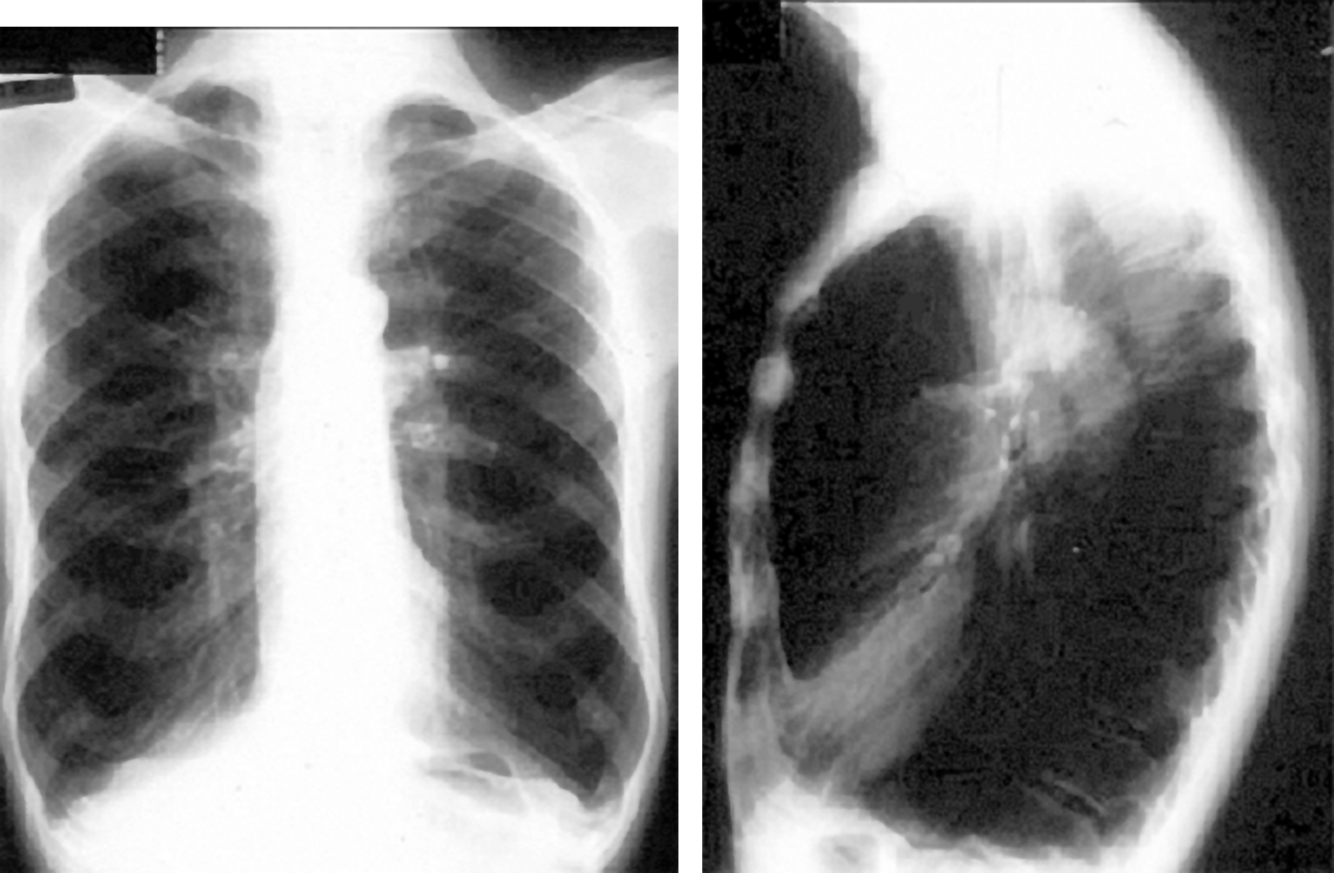

34yo male with cough of 10 days duration

View:

DX:

View: PA/lateral

DX: lobar pneumonia - RUL